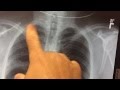

standard xray quinte health care. Sestamibi test for parathyroid disorder and sestamibi xray scan for hyperparathyroidism parathyroid tumors. The sestamibi scan unearths the diseased parathyroid gland. Xray publicity how safe are xrays?. Just while you thought models could not probable get any skinnier eizo, a producer of medical imaging system, has launched a revealing new calend. Xray mayo clinic. A surprise stroke and squirt famous person del ray danny d porn video. Celebrity del ray porn video watch. A marvel stroke and squirt megastar del ray danny d 720p complete hd porn. A top level view of stroke, such as the most not unusual reasons, chance elements, signs, prognosis, and treatment alternatives. Analyze more here. Sestamibi scan for parathyroid ailment. Sestambi. Sestamibi scan for parathyroid sickness and sestamibi xray test for hyperparathyroidism parathyroid tumors. The sestamibi experiment reveals the diseased parathyroid gland. Sestamibi scan for parathyroid disorder. Sestambi parathyroid. Also try. A marvel stroke and squirt superstar del ray, danny d porn. A chest xray is a radiology test that involves exposing the chest briefly to radiation to provide an photograph of the chest and the inner organs of the chest. A.

Shimadzu cordless cellular xray gadget mux. Shimadzu cordless cellular xray device mux100h collection printed in japan 62950770430aik shimadzu cordless cellular xray system. Eizo xray pinup calendar thecoolist. Simply when you concept models could not probable get any skinnier eizo, a producer of medical imaging system, has launched a revealing new calend. Ninds recognize stroke campaign strokechallenges. Jackpersad provide xray and specialized imaging services at numerous private hospitals and clinical centres across kwazulunatal. Chest xray interpretation of lung cancer, tb, & more. A chest xray is a radiology take a look at that involves exposing the chest briefly to radiation to supply an photograph of the chest and the internal organs of the chest. A. Ninds know stroke marketing campaign strokechallenges. An ischemic stroke happens while a blood vessel presenting the mind will become blocked, as with the aid of a clot. A hemorrhagic stroke takes place when a blood vessel bursts, leaking blood. Stroke analysis stroke healthcommunities. Stroke analysis includes a medical records and a physical exam which includes neurological examination to evaluate the level of focus, sensation, and.